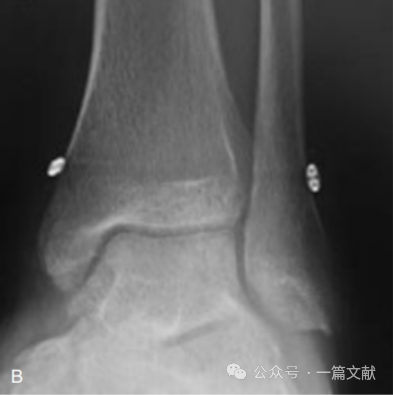

3,弹性固定:很多研究显示,相较于常规螺钉固定,弹性固定并没有明显优势。如下图,